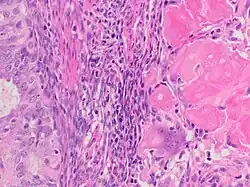

Squamous growth seen as necrotic “ghost cells” of keratinocytes at right in image, leaving pink keratin.